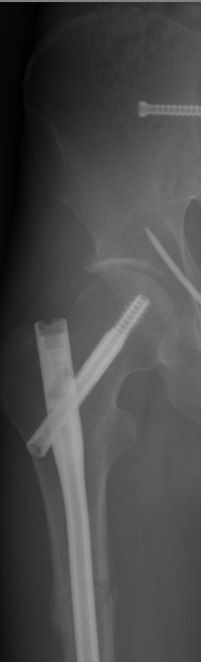

На картинке вы видите стержень внутри бедренной кости. Слева вверху - головка бедренной кости. Толстый винт, который идет через стержень в головку - шеечный винт. Он не дает стержню смещаться. Перелом здесь, если не ошибаюсь, чрезвертельный

Вы видите на картинке линию перелома, которая идет от большого вертела к малому? Для того, чтоб вам было понятнее, приведу картинку строения бедренной кости